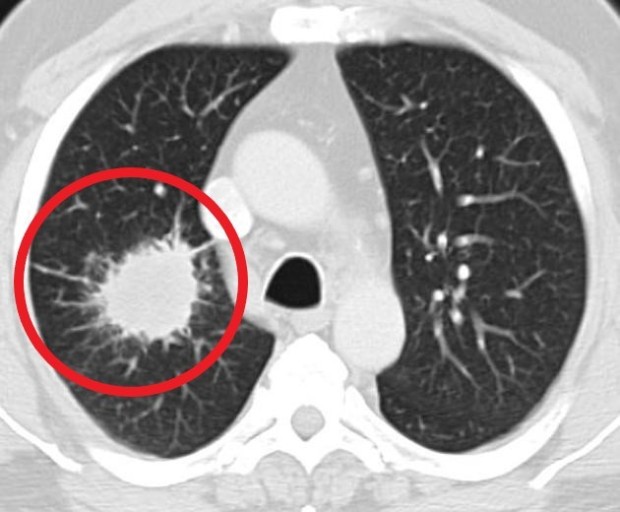

폐암은 위암, 갑상선암 다음으로 3번째로 발병 빈도가 높은 3대 암 중 한 가지인데요. 폐암은 재발과 전이까지의 빈도도 잦은지라 완치가 어렵다고 하며 폐암 발병 초기에는 거의 증상이 없을 수가 있어 수술이 불가능한 3기, 혹은 4기에 주로 진단된다고 해요.

폐암 초기증상 폐암 4기에 이르게 되면 5년 생존률이 30% 대로 감소하게 된다고 해요. 그리하여 폐암은 암 질병이자 중 사망자 비율이 가장 높은 것으로 나타나고 있어요.

폐암은 사망률 2위를 차지하고 있는 간암에 비해 무려 2배에 가까운 사망률을 보이고 있다고 합니다. 이렇게 치명적인 폐암에 대해 미리 알고 대처하는 것이 바람직할 것 같아요. 아래에서는 폐암이라 판단해 볼 수 있는 그 초기증상에 대해 간단히 설명드릴게요.